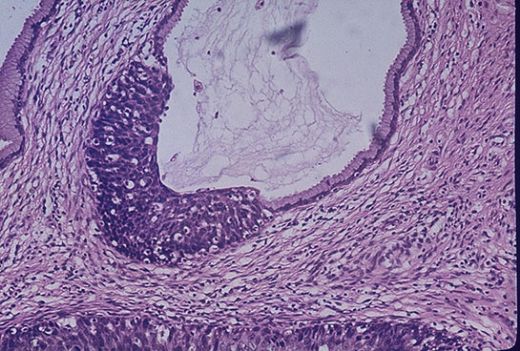

İdrarda Yassı Epitelin Olması Nedenleriİdrar, vücuttan atılan sıvı atıkların ve toksinlerin birikmesiyle oluşan önemli bir biyolojik sıvıdır. İdrar, çeşitli hücre tiplerini içerebilir ve bu hücrelerin varlığı, bazı sağlık durumlarının göstergesi olabilir. Bu bağlamda, idrarda yassı epitel hücrelerinin bulunması, belirli tıbbi durumlardan kaynaklanabilir. Bu makalede, idrarda yassı epitelin varlığının nedenleri detaylandırılacaktır. Yassı Epitel Nedir?Yassı epitel, hücrelerinin düz ve ince olduğu, genellikle bir tabaka halinde düzenlendiği bir epitel tipidir. Bu tip epitel doku, özellikle vücutta çeşitli organların yüzeylerini kaplama işlevi görmektedir. İdrar sisteminde, yassı epitel genellikle idrar kanallarında ve mesanede bulunur. Yassı epitel hücreleri, idrarın geçişi sırasında mekanik bir bariyer oluşturarak, enfeksiyonların önlenmesine ve sıvı dengesinin korunmasına yardımcı olur. İdrarda Yassı Epitelin Görülme Nedenleriİdrarda yassı epitel hücrelerinin varlığı, çeşitli nedenlerden kaynaklanabilir. Aşağıda, bu nedenler detaylandırılmıştır:

Yassı epitel hücrelerinin idrarda görülmesi, normal sınırlar içinde bile önemli bir durumdur. Bu hücrelerin varlığı, genellikle idrar yollarında bir irritasyon veya enfeksiyon belirtisi olabilir. Sağlıklı bireylerde, belirli bir oranda yassı epitel hücresinin bulunması normal kabul edilse de, bu oranların aşılması, idrar yolu enfeksiyonları (İYE) veya diğer sağlık sorunlarının habercisi olabilir.

Yassı epitel hücrelerinin aşırı miktarda bulunması, idrar yolu enfeksiyonu, böbrek taşları veya mesane irritasyonu gibi durumların gelişimine yol açabilir. Bu tür sorunlar, idrar yaparken yanma, sık idrara çıkma ve bel ağrısı gibi belirtilerle kendini gösterebilir.